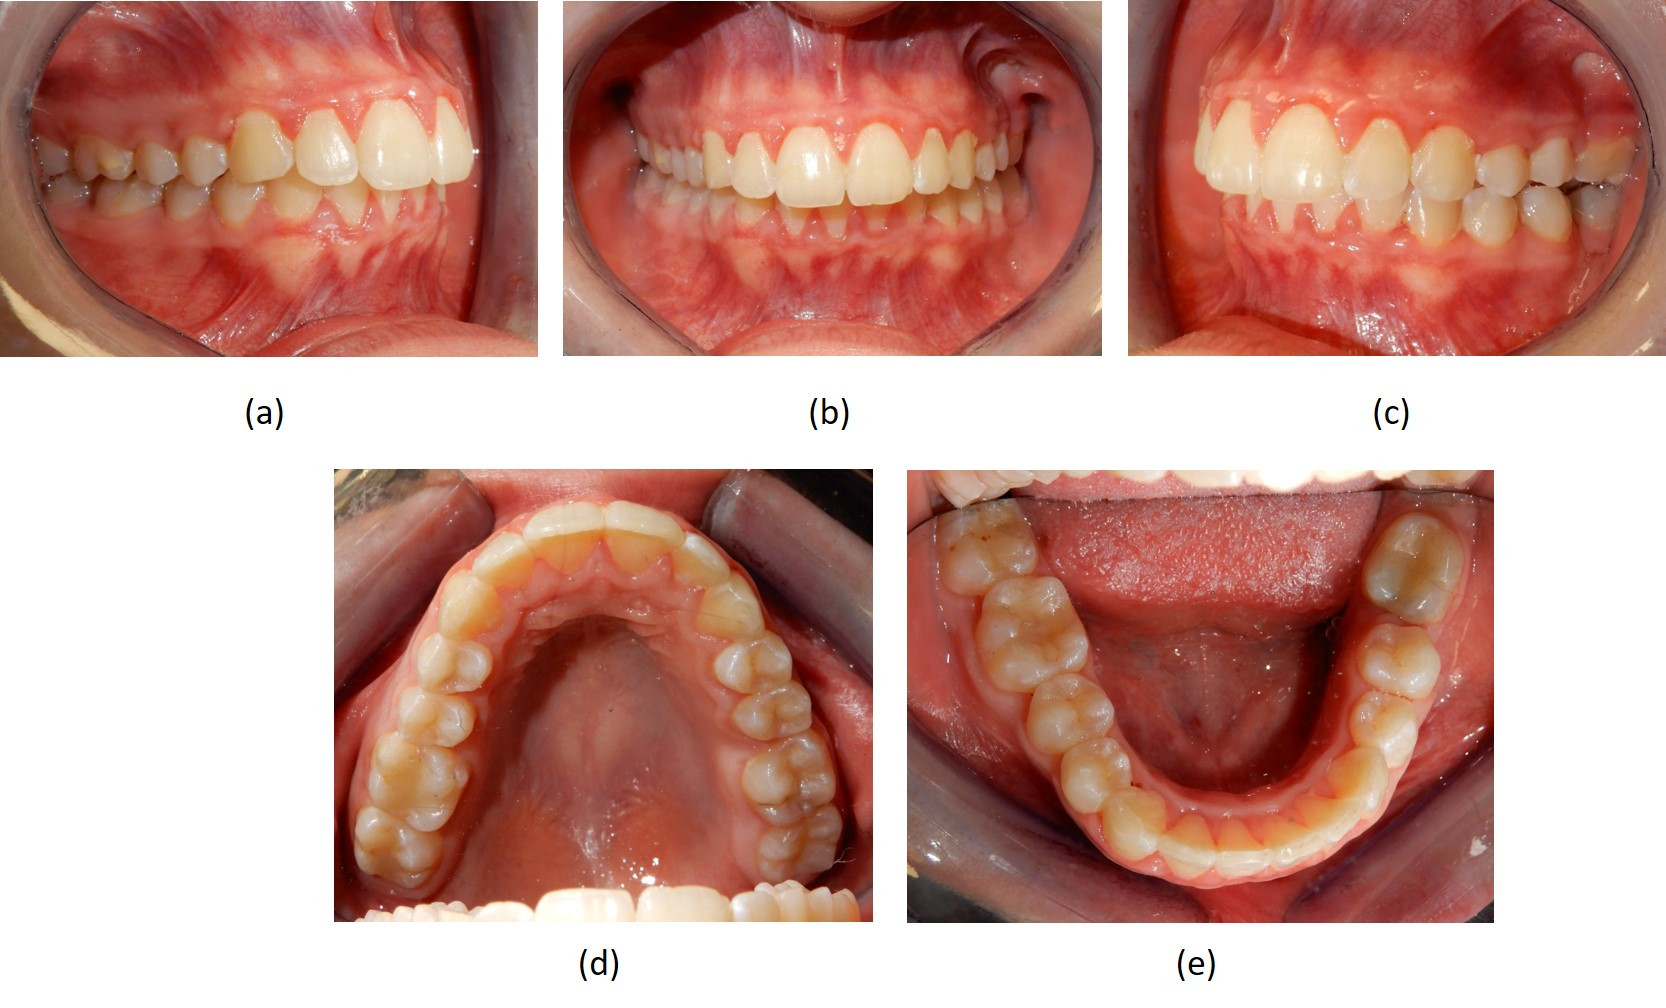

Fotografie intraorali  pre-trattamento

Fig. 3 Fotografie intraorali  pre-trattamento. (a) visione laterale destra; (b) visione frontale con morso profondo; (c) assenza dei due primi molari sul lato sinistro; (d) visione occlusale superiore che mostra l'assenza del primo molare sinistro; (e) visione occlusale inferiore che mostra sul lato sinistro l'assenza del primo molare e l'affollamento moderato degli incisivi